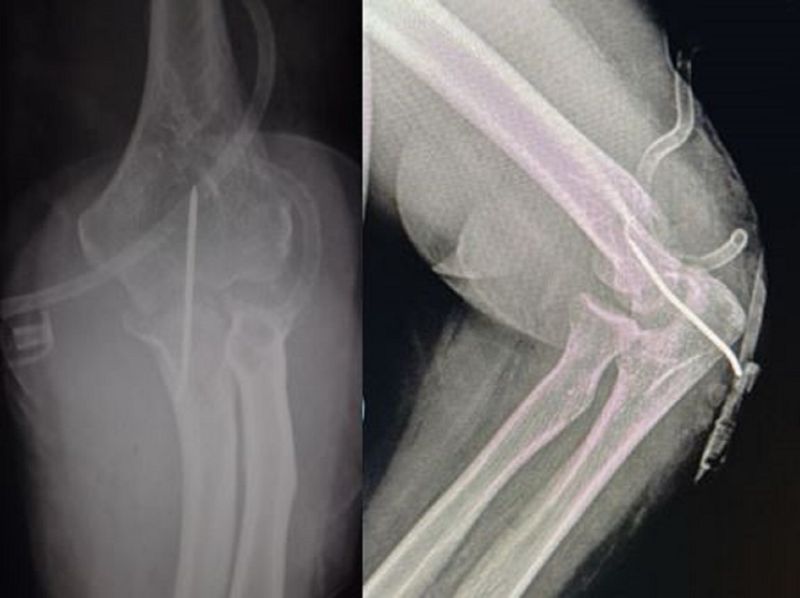

An X-ray of the elbow with AP and lateral views as seen in Figure 1 revealed a posterior dislocation of the elbow with heterotopic ossifications. The patient was hospitalised and pre-operative bloodwork was done in preparation for a surgical reduction.

Figure 1: posterior elbow dislocation with osteophytes in the olecranon fossa and trochlear notch